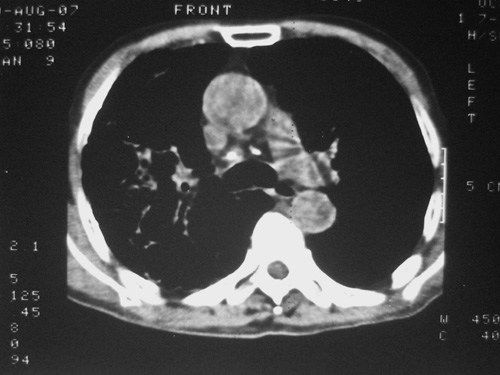

老年男性,70岁。煤矿工人20年。一周前咳嗽、发烧,拍x片考虑矽肺可能。始终咳嗽行ct检查,发现弥漫性病变,似感染但密度很高,细支气管肺泡癌无法排除,请老师给予指点。

一般矽肺多为双肺融合状,团块状高密度结节影.并散在多处小结节影.可这个病人只表现在单肺,并没有融合结节影.一周前的x片没显示大片高密度影,可定位扫描时(图象忽略传了),右肺已经清晰显示大片高密度影.作比较感觉是新病灶.可实际表现又不象,所以才拿来让各位老师看看.

矽肺,两肺间实质炎症,蜂窝肺。

矽肺  两肺间质性炎症伴纤维化(蜂窝肺)

患者病程较短,有明显咳嗽发热症状,结合病史考虑矽肺合并以间质为主的肺感染,肺泡癌先放下,抗炎再说

ct片与平片只相隔1周时间变化太大,结合临床应该首先考虑尘肺合并感染,肺泡癌变化不会这么快,